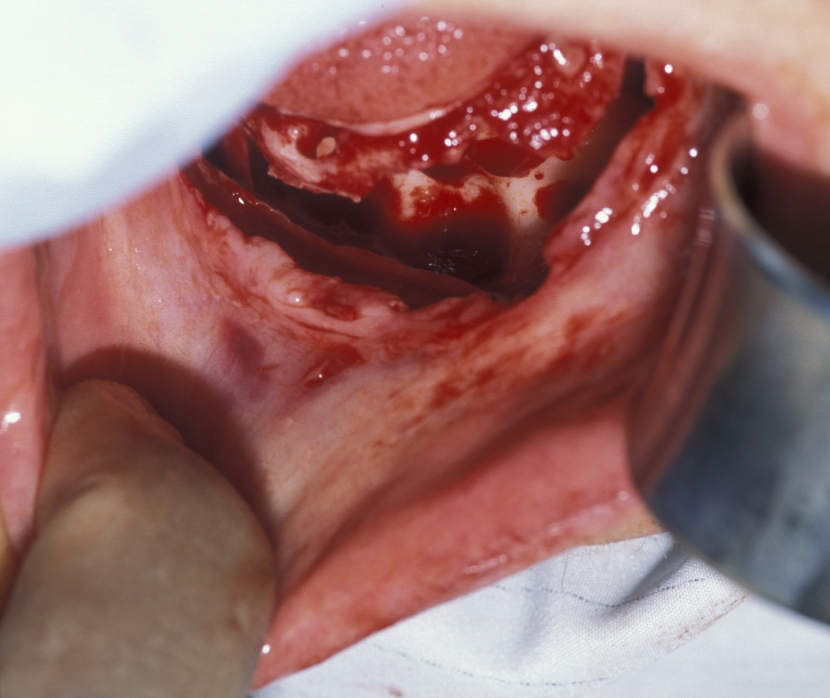

Figure 1: Flap to expose bone expanded by the underlying cyst.

Figure 2: Buccal cortex (outer hard shell of bone) is removed to create a bone window for enucleation of the cyst.

Figure 3: The plane between the cyst lining and the bone cavity is bluntly dissected.